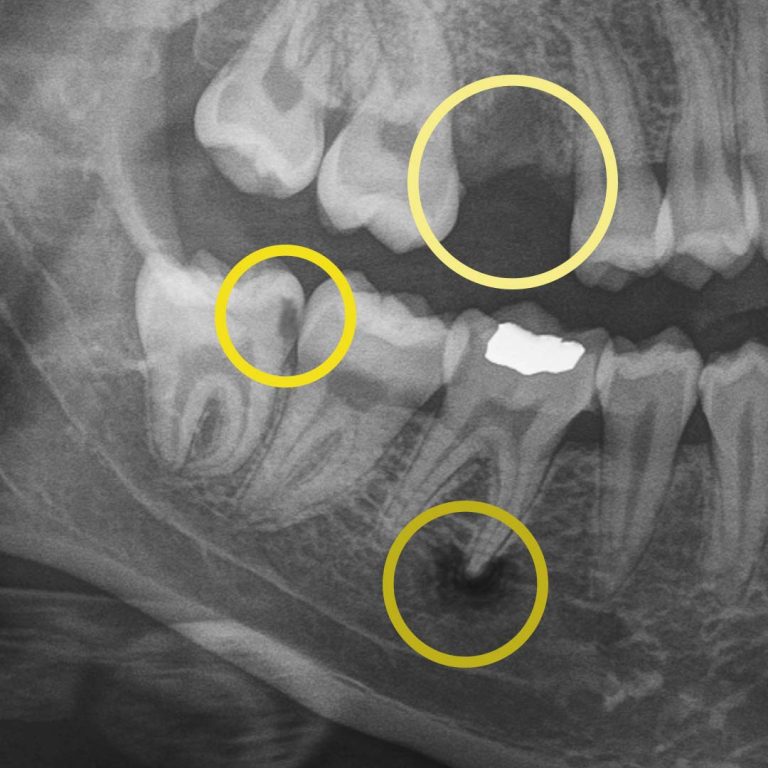

Digital X-rays allow us to look beyond what’s visible. They help us detect:

• cavities between teeth.

• early decay hiding under fillings or crowns.

• bone changes related to gum disease.

• infections at the root of a tooth.

• subtle cracks.

For example, during a routine digital X-ray, we may notice a small shadow between two teeth. To the naked eye, everything can look healthy, but that faint shadow often tells us the enamel in that area is starting to weaken. This is considered early-stage tooth decay, sometimes called early “caries.”

At your next X-ray visit, we’ll compare images to see whether that spot has stabilized or improved. If the area worsens and the enamel breaks down further, a small dental filling may be necessary to prevent deeper decay damaging the tooth structure. If the decay continues unchecked and reaches the inner portion of the tooth where the nerve lives, treatment becomes more complex, often requiring root canal therapy, which can be time-consuming, uncomfortable, and costly.